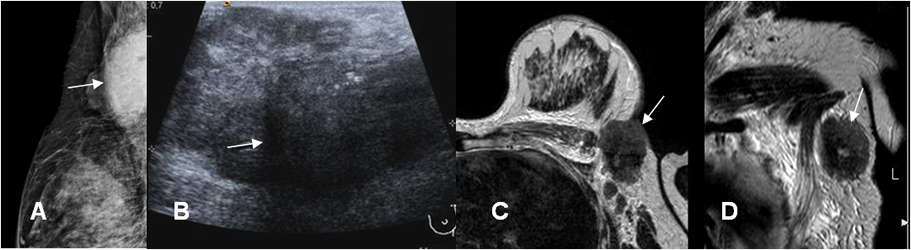

Fig 14. Neo de mama.

A: Mamografía mediolateral. Imagen ovalada y densa, que compromete la región axilar.

B: Ecografía. La lesión es hipoecoica y de bordes parcialmente definidos. Presenta algunas calcificaciones, en su parte superior.

C: RM axial en T2 y D: RM coronal en T2. Lesión hipointensa a nivel de la axila y cuya patología reveló un tumor de mama metastásico.